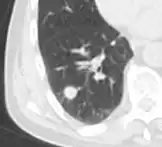

A lung nodule or pulmonary nodule is a relatively small focal density in the lung. A solitary pulmonary nodule (SPN) or coin lesion,[1] is a mass in the lung smaller than three centimeters in diameter. A pulmonary micronodule has a diameter of less than three millimetres.[2] There may also be multiple nodules.